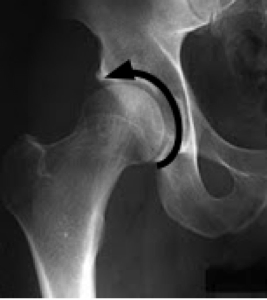

Notice, in the X-ray above, the deep socket and especially the very definite lower margin of the acetabulum.

In the X-ray below of DDH, there is a shallow socket, with a sloping upper margin instead of a proper roof. In addition the lower margin of the acetabulum is barely seen.

Notice, in comparison with the normal hip above, how a much larger portion of the ball protrudes beyond the socket; it is un-roofed, and cannot contribute to bearing the weight of the body. The nett result is that the weight of the body is concentrated on a much smaller area of cartilage between the ball and socket, with far greater stress on the hyaline cartilage and underlying bone.

Notice too, instead of a nice round ball, the flattened, 'mushroom-shaped' medial margin of the ball; this is a finding common to several hip abnormalities.

Notice again in the X-ray below the various features of Developmental Hip dysplasia. The sloping socket, the large unroofed part of the ball, the flattened femoral head, the wide margin in the lower part of the hip, and now, in this slightly older patient, the beginning of 'sclerosis' on both the roof of the socket and the ball. This is hip arthritis in the making.

This patient already has pain in the groin radiating down the inner thigh muscles, pain on the side of the hip, and sacro-iliac joint pain. She also has short leg causing a tilted pelvis and a curvature of the spine. Undiagnosed Development Hip Dysplasia causes a leg length inequality.